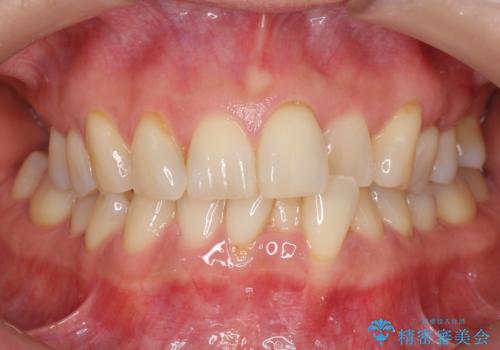

歯並びや奥歯の痛み 色々と治したい 総合歯科診療

担当医 藤巻太一朗

インプラント治療・セラミック治療を含む 全顎的虫歯治療

担当医 大元洋佑